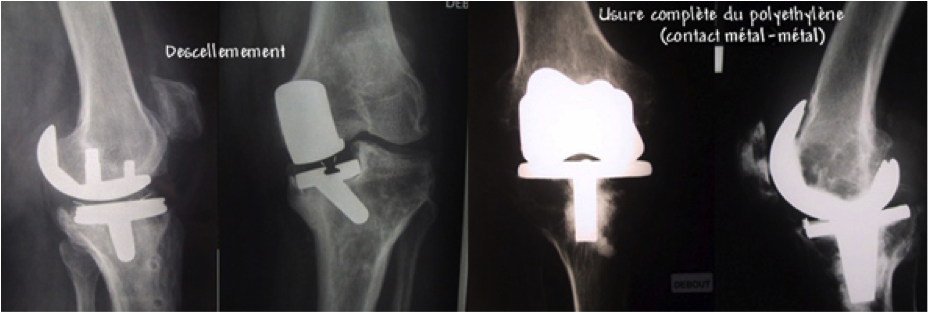

• Descellement : sans cause apparente ou en cas de surcharge pondérale ou de surutilisation, pouvant conduire à un remplacement anticipé

• Usure de la prothèse : durée de vie espérée de 15 à 25 ans, variable d'un patient à l'autre et influencée par le degré de contrainte de la prothèse

Reprise de prothèse totale du genou